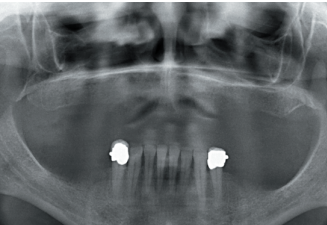

It shows that there is apparently some height in the maxillary ridge both anterior and posterior and a low dental nerve in the jaw that allows us to have a greater residual bone crest available for the insertion of the implants (Figure 3).

Subsequently, we proceed to perform a dental cone beam that offers a more accurate view of the type of implant rehabilitation that can be proposed. In the sections corresponding to the upper maxilla, there are areas where the direct insertion of the implants can be performed such as those corresponding to 16 and the central incisor zone of this quadrant (Figures 4-5) or in the second quadrant the area of the 27.

implant rehabilitation that can be proposed. In the sections corresponding to the upper maxilla, there are areas where the direct insertion of the implants can be performed such as those corresponding to 16 and the central incisor zone of this quadrant (Figures 4-5) or in the second quadrant the area of the 27. On the other hand, in the area corresponding to teeth 21 and 23 there is a significant horizontal atrophy, with a residual bone width of approximately 3.5 mm in the middle zone of the crest, with an enlargement in the most basal area of the same and conservation of both corticals. This leads to choose a split crest technique, in this case in two phases to achieve a greater final width and correct the inclination of the final implant as much as possible to achieve adequate aesthetics in the final prosthesis (Figure 6).

In the areas corresponding to teeth 11 and 13 the horizontal atrophy is even more marked. There is no trabecular bone separating the two corticals (vestibular and palatine) and the width is less than 2mm in some areas which is why block grafts are planned in this area. Short implants are planned in the mandible by direct insertion, and the area corresponding to the mandibular branch will be the donor area for the block grafts.